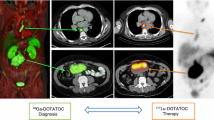

Originally developed in Basel, Switzerland, the synthetic somatostatin analogue edotreotide (or DOTATOC) has been evaluated and clinically used in combination with Yttrium-90 for the therapy of somatostatin receptor-positive tumours. Currently, Ga-68-edotreotide PET imaging agents are approved in Europe and in the USA for visualisation of neuroendocrine tumours (NETs). Excellent pharmacokinetic properties of this peptide combined with the outstanding characteristics of Lutetium-177 make it even more attractive for therapeutic use.

Following on from the Bad Berka study [7], ITM has initiated a Phase III pivotal clinical trial. COMPETE is a prospective, randomised, open-label multi-centre Phase III study to evaluate the safety and efficacy of 177Lu n.c.a.-edotreotide in comparison to everolimus in patients with G1 and G2 GEP NETs. The patients have progressive, somatostatin receptor (SSTR) positive disease on SSTR imaging. Uniquely, patients may be included as first-line therapy. There are 3 sub-studies which focus on 177Lu-edotreotide dosimetry and pharmacokinetics. These sub-studies are of great importance in the development of a personalised, precision therapy approach to the management of patients with PRRT. In addition, 177Lu is uniquely non-carrier-added, which means that it is a pure radionuclide of high specific activity.